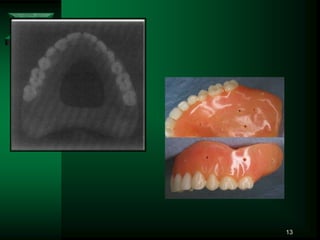

13

• #14 A large part of the middle of the palatal portion of the maxillary denture is removed for visibility in positioning the maxillary denture during the impression making.